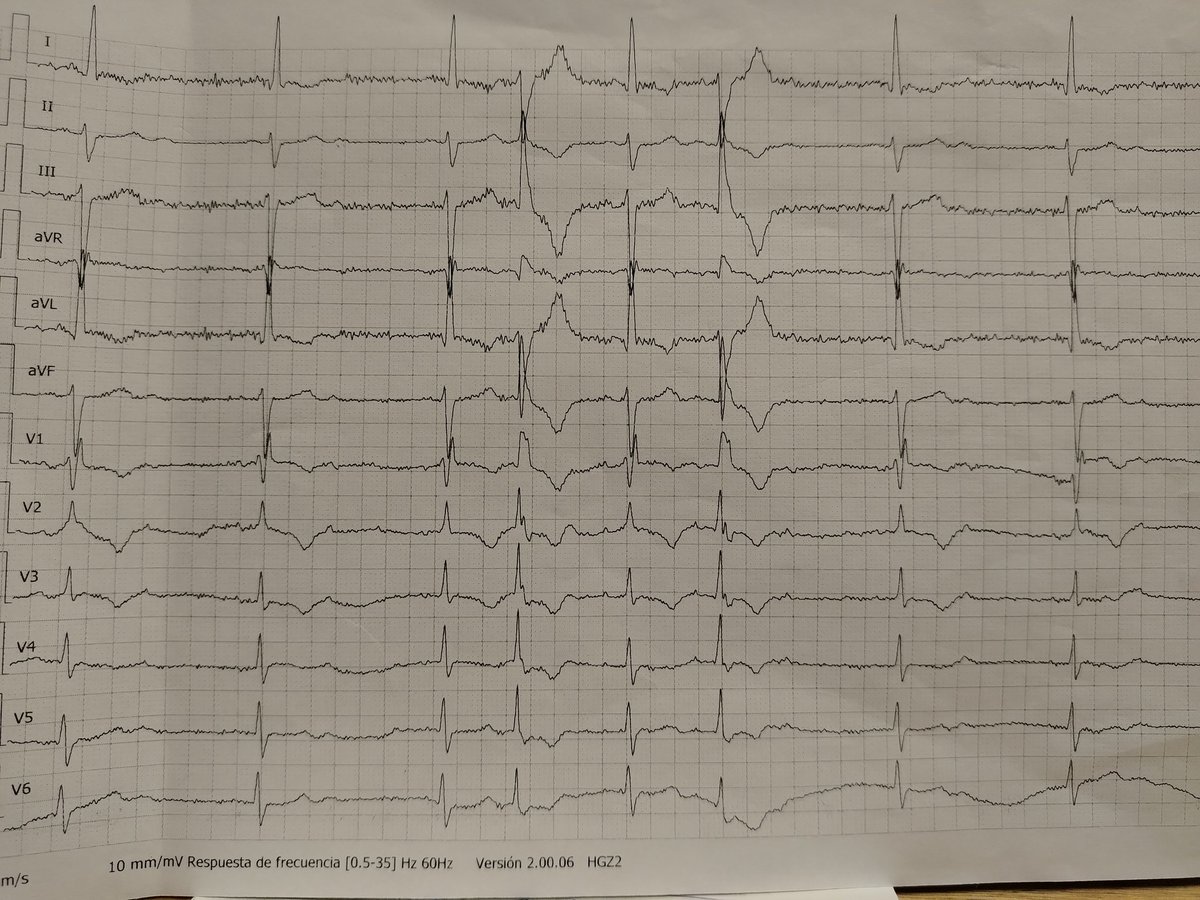

59 M came in due to Right Midaxillary pain with Chronic tophaceous gout and HTN of 210/120.

Anteroseptal MI?

Chest pain. Thoughts?

ECG alert 🚨 Regular wide complex tachycardia.

QRS >120 ms.

Hemodynamically stable.

Is this:

• Ventricular Tachycardia or

• SVT with aberrancy ?

What’s your reasoning?